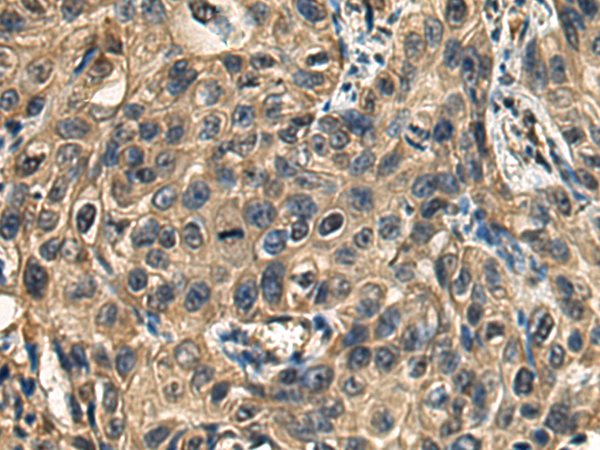

分类: 科研抗体货号: P08886别名: DESC1; TMPRSS11E2应用: IHC反应种属: Human